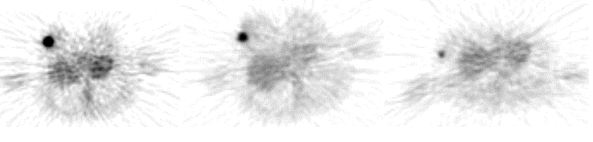

Hình ảnh FLT - PET K vú trước ĐT; (b): Hình ảnh FLT - PET K vú sau ĐT, ổ hấp thu PX cao trước ĐT đã biến mất.